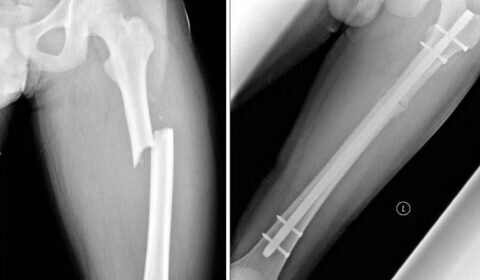

Так как перелом диафиза в бедренной кости часто сопровождается осложнениями и смещениями, может потребоваться проведение операции. Целью хирургического вмешательства является остеосинтез с параллельным восстановлением целостности сосудов и мягких тканей.

Для соединения диафизарных фрагментов могут применяться костные фиксаторы (штифт, пластины, гвозди и винты), а также наружные приспособления. Довольно часто применяется интрамедуллярный ретроградный метод остеосинтеза с внутрикостным введением штифта, который остается навсегда в конечности пациента. Его вбивают в заранее подготовленное отверстие в костномозговом канале, а конец со стороны введения в вертельную ямку фиксируется винтами.

После завершения репозиции и остеосинтеза рану зашивают, соединяя послойно мягкие ткани и сосуды. Дополнительно устанавливается дренаж, минимум на 1 сутки. Дальнейшее лечение производится в стационаре, пока состояние пациента не стабилизируется.